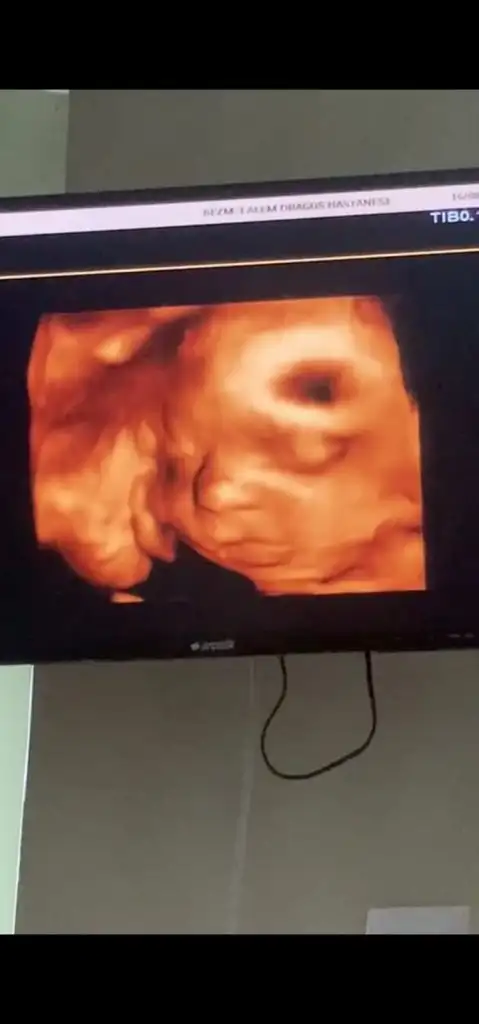

artık 15 de bir gidicem artık, benim uzunluktan ziyade kafa pozisyonu çok çok aşağıda. O yüzden yüzünü görmek imkansız gibi bir şeymiş artık